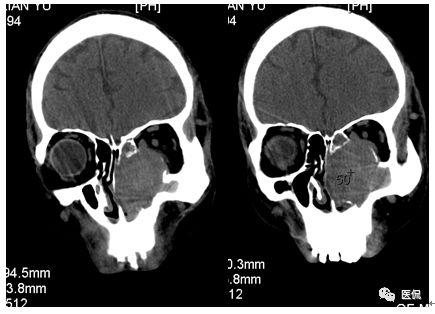

CT平扫及增强示:左侧上颌窦及鼻腔可见软组织密度影,呈膨胀性生长,周围骨质压迫性吸收破坏,累及左眶,病灶密度不均匀,周边区可见点状钙化,增动脉期轻度强化,局部见小灶性稍高密度区,静脉期病灶内见不均匀明显强化,CT值最高达117HU,延迟期强化范围有所增大。

本例病灶较大,周围骨质可见吸收破坏,并累及眼眶,病灶内少量钙化,增强扫描具有一定特征性,表现为动脉期轻度强化,局部见小灶性稍高密度区,静脉期病灶局部呈明显强化,CT值最高达117HU,延迟期强化范围有所增大,呈延迟渐进性强化的特点,推测为病灶内出血所致。